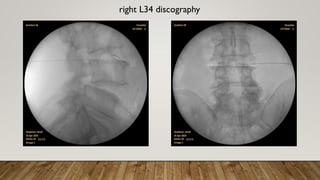

right L34 discography

right L45 discography with epidural spreading